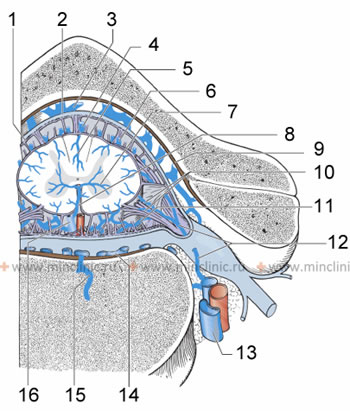

1 – ქსელისებრი გარსი, 2 - ტვინის მაგარი გარსი, 3 - ხერხემლის უკანა გარე ვენოზური წნული, 4 - ზურგის ტვინის უკანა ვენა, 5 - უკანა ცენტრალური ვენა, 6 - ზურგის ტვინის უკანა -გვერდითი ვენები, 7 - სულკოკომისურალური ვენა, 8 - ღარის ვენა, 9 - ძვლისზარდელა, 10 - წინა და უკანა ფესვური ვენები, 11 - ზურგის ტვინის წინა შიდა ვენოზური წნულები, 12 - მალთაშუა ვენა, 13 - მალების ვენები, 14 - ზურგის ტვინის წინა გარე ვენოზური წნული, 15 - ბაზალურ-ვერტებრალური ვენა, 16 - ზურგის ტვინის წინა ვენა.